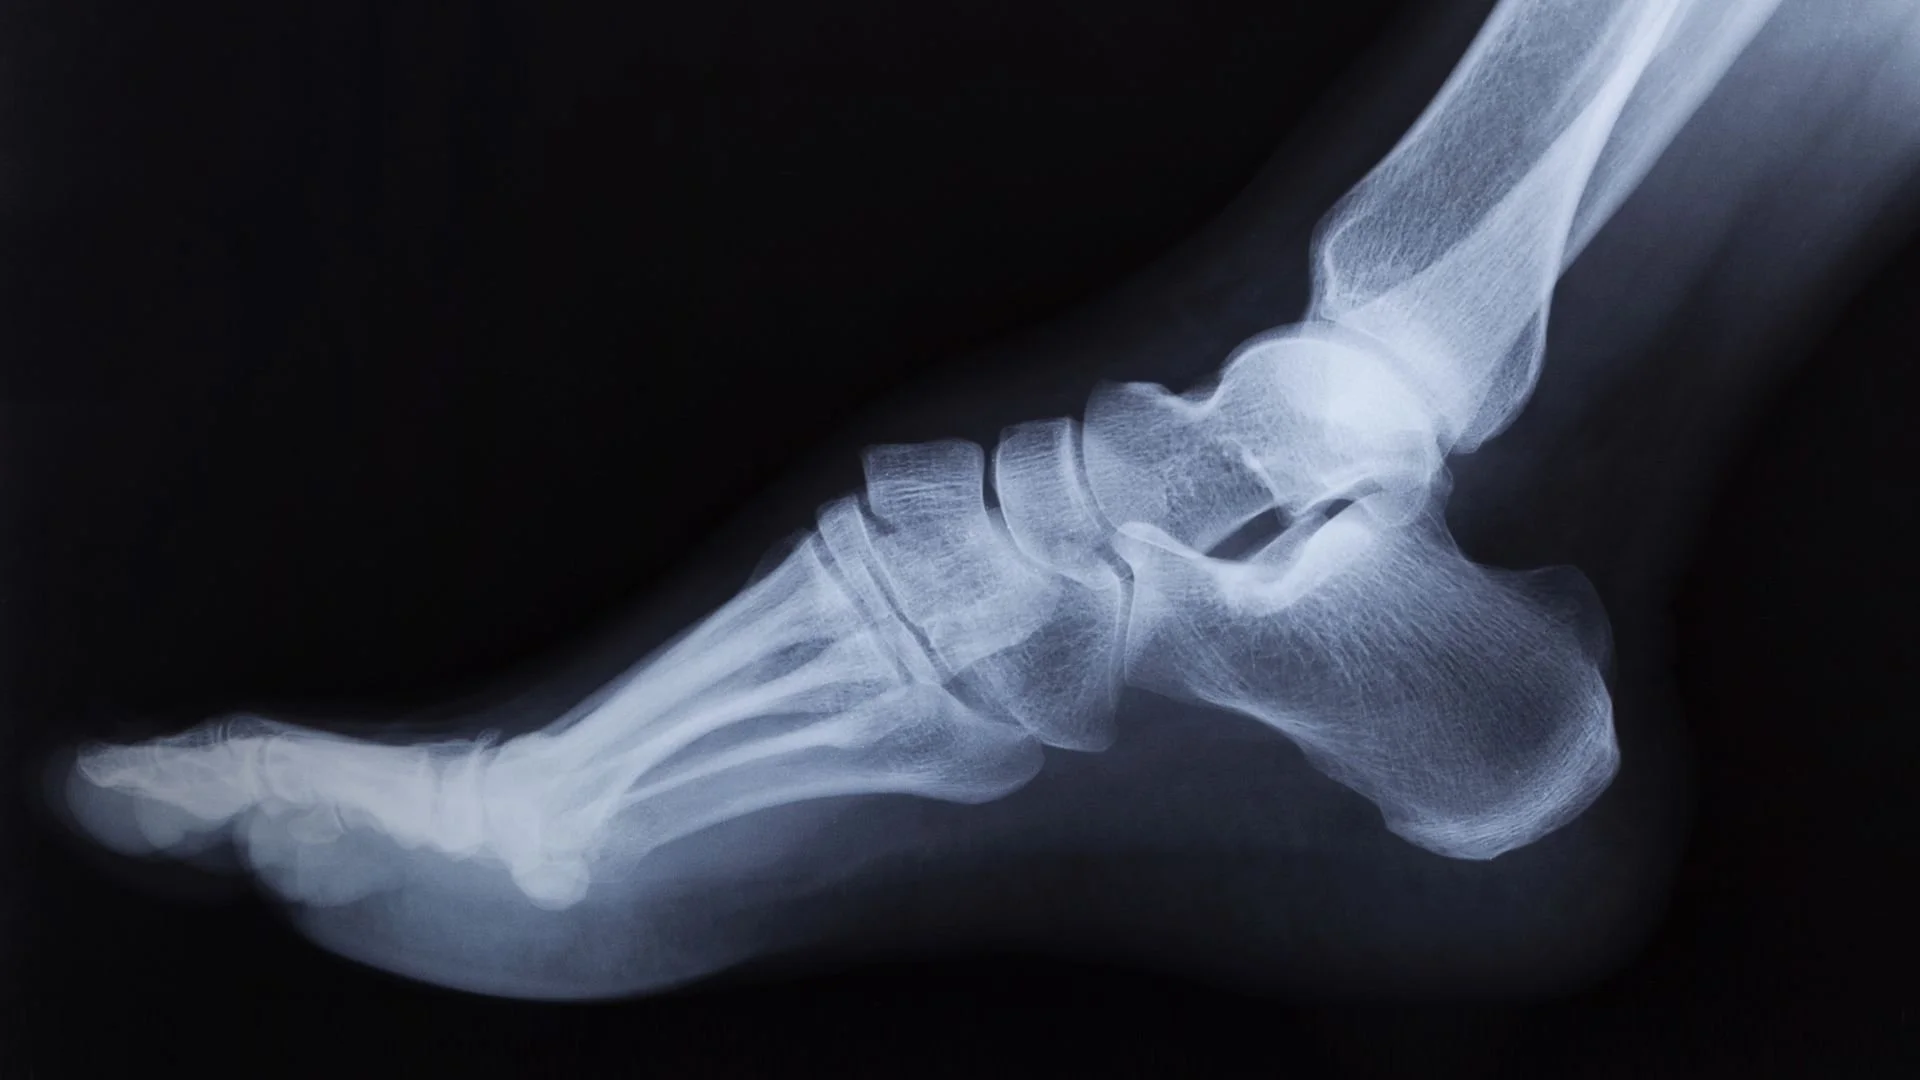

Imaging and focal point testing are two ways we can identify stress fractures in the metatarsal region.

Testing for Stress Fractures Using Imaging and the Focal Point Assessment

In our office, we use advanced imaging to look for the fluffy white cloud of a bone callus, which is the sign that your body is desperately trying to heal a crack. However, because early-stage stress fractures often don't show up on a standard X-ray for 2–3 weeks, we also rely on a clinical focal point test.